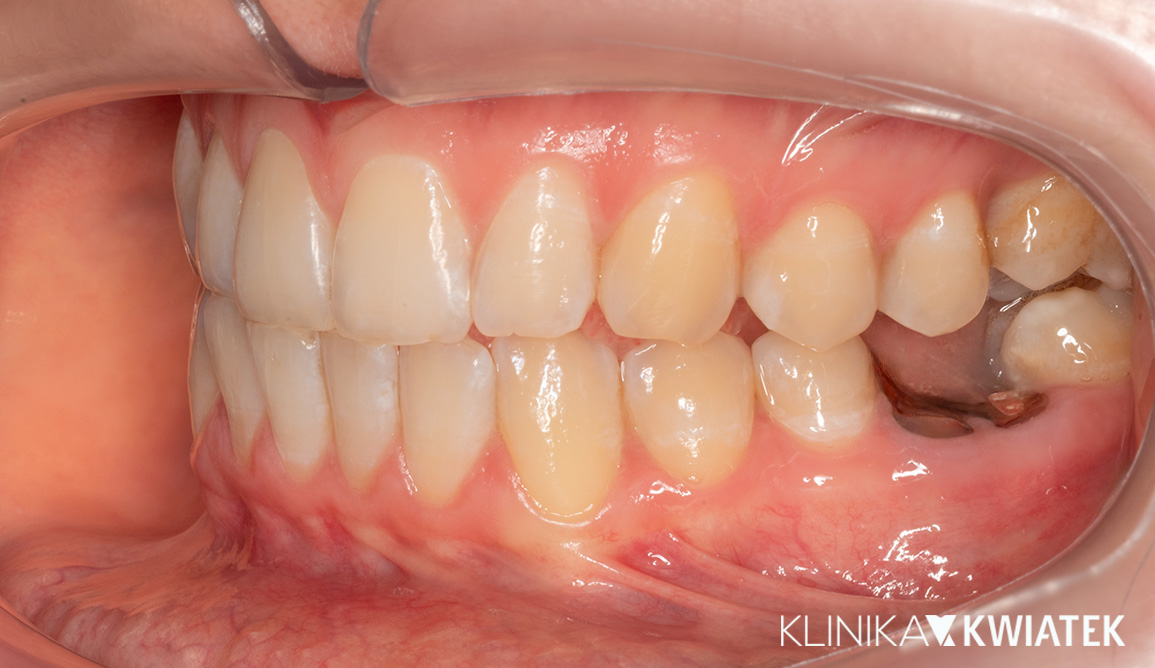

PRZED

PO

Pacjentka zgłosiła się z wadą zgryzu, licznymi ubytkami i utraconymi zębami trzonowymi, co powodowało trudności w żuciu i estetyczne niezadowolenie. Leczenie obejmowało ekstrakcje, ortodoncję, implantację oraz kompleksową rekonstrukcję protetyczną. Po kilkunastu miesiącach terapii Pacjentka odzyskała pełną funkcję zgryzu i piękny, harmonijny uśmiech.